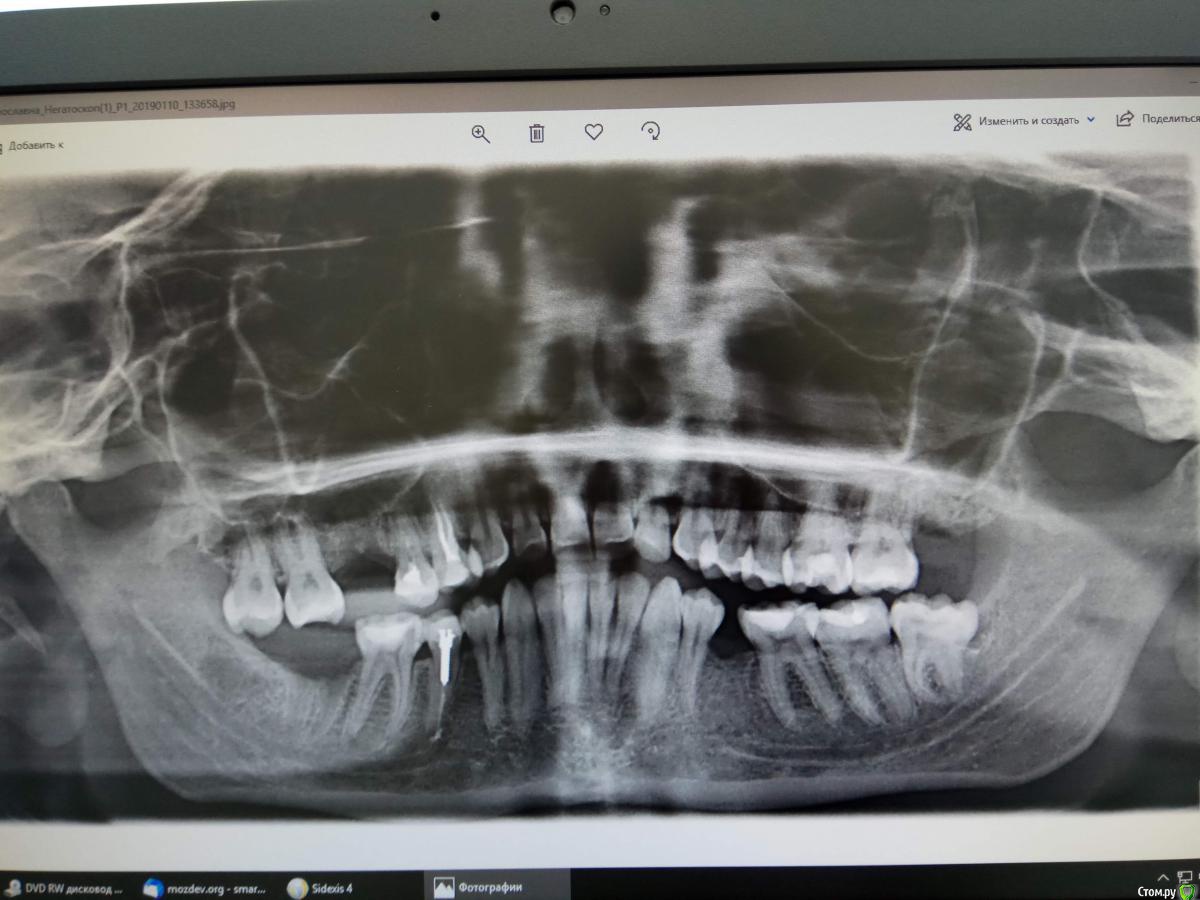

St. Опубликовано 5 января, 2019 Поделиться Опубликовано 5 января, 2019 Добрый день. Для начала сделайте панорамный снимок всех зубов в цифровом формате чтоб можно было видеть исходную ситуацию на сегодняшний день 3 Ссылка на комментарий

slavna_she Опубликовано 10 января, 2019 Автор Поделиться Опубликовано 10 января, 2019 (изменено) Такой формат подойдёт? Это все, что в клинике мне смогли предоставить Изменено 10 января, 2019 пользователем slavna_she Ссылка на комментарий